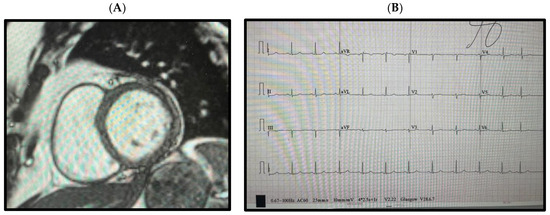

2. Clinical History